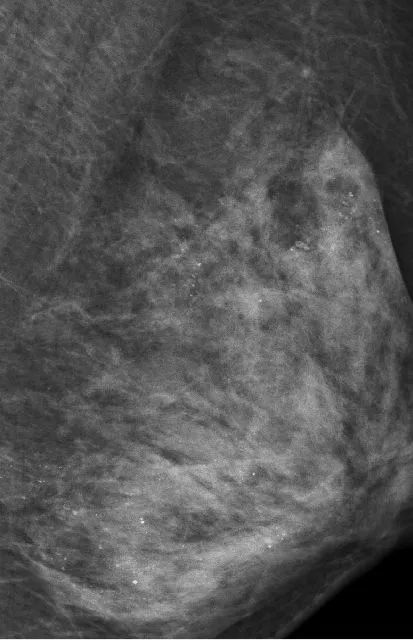

最让医生意外的是她的左侧乳房。乳腺X线检查时,发现里面全部都是细小如沙子一样的钙化灶,布满整个乳腺。

在X光片下,朱女士的乳腺里满是星星点点的钙化灶

让管床医生陶龙犯难的是,如此多的细小钙化灶,无法判断哪些是良性哪些是恶性。

乳腺沙砾样钙化灶是乳癌的信号之一,需要高度关注。